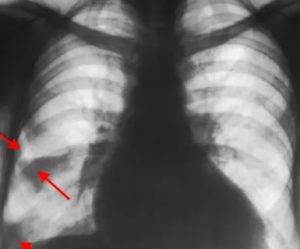

На рентгене прослеживается характерное треугольное затемнение с основанием к периферии легкого в средних и базальных сегментах. Однако, выраженный венозный застой и отек паренхимы могут сглаживать рентгенологические проявления.

Важно! При реализации рентгенографии на снимке видны затемненные области на пораженном легком.

Инфаркт легкого диагностируется с помощью рентгена, так как только с его помощью обнаруживается высокое положение купола диафрагмы, то, насколько расширены корни одного из легких, плевральный выпот, и некоторые другие отклонения.